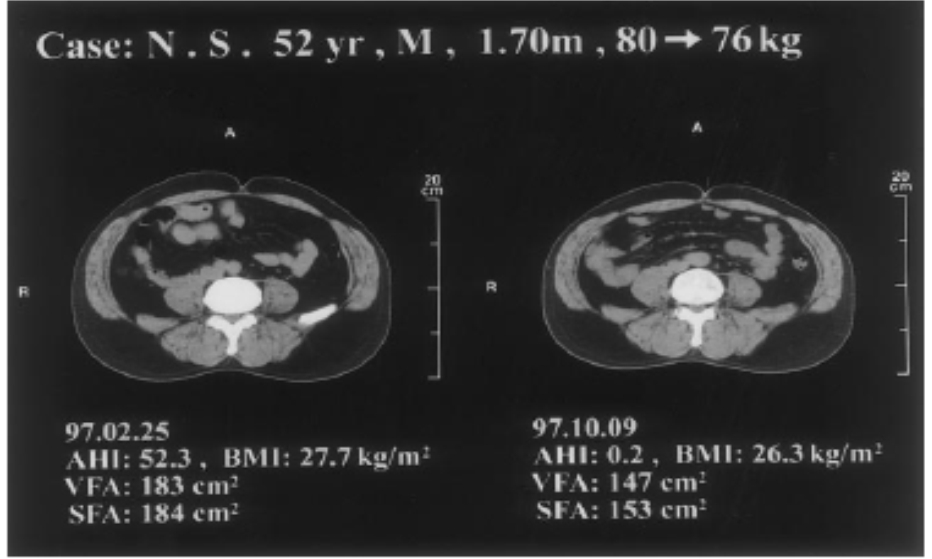

По результатам некоторых исследований CPAP терапия не оказывает положительного влияния на метаболизм глюкозы. В частности, рандомизированное, плацебо-контролируемое, перекрестное исследование Coughlin et al. (Объединенное Королевство) не выявило изменений инсулинорезистентности, но обнаружило значительное улучшение дневного артериального давления и чувствительности барорецепторов после 6 месяцев CPAP терапии [25]. Авторы предположили, что длительность CPAP терапии, необходимая для изменения сердечно-сосудистых и метаболических показателей, может быть различной и для нормализации метаболизма требуется более длительное время CPAP терапии. Результаты исследований по влиянию CPAP терапии на метаболизм глюкозы могут быть противоречивы вследствие различий в количестве исследуемых, длительности CPAP терапии и методов ее оценки, изменения строения тела в течение периода исследования. В частности есть данные об уменьшении висцерального жира в результате длительной CPAP терапии. Chin et al. (Япония) оценивали изменение висцерального и подкожного жира посредством компьютерной томографии у больных с ОАС до и после 6 месяцев CPAP терапии [26]. На рис. 2 приведены данные одного из больных, вовлечен-ных в исследование. Компьютерная томография на уровне пупка показала уменьшение объема висцералного жира с 183 до 147 см2, а подкожного – с 184 до 153 см2 после 6 месяцев CPAP терапии. Авторы сделали заключение: длительная CPAP терапия больных с ОАС приводит к значительному и достоверному снижению массы тела, висцерального и подкожного жира и может быть применена именно с этой целью.

Рис. 2. Компьютерная томография живота на уровне пупка у больного с ОАС до (а) и после (в)

6 месяцев CPAP терапии. Зафиксировано уменьшение массы, висцерального (VFA) и подкожного (SFA) жира [26].